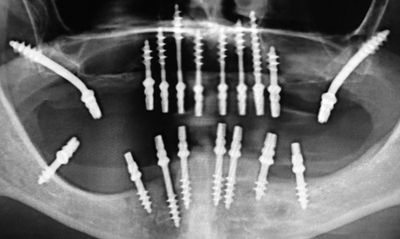

BASAL IMPLANTS

These are single piece implants where abutment and screw are fused together. Basal implantology, also known as bicortical implantology or just cortical implantology, is a modern implantology system which utilizes the basal cortical portion of the jaw bones for retention of the dental implants. Basal bone is less prone to bone resorption and infections. Basal bone is highly dense, corticalized, and offers excellent support to implants. These implants are designed in one piece that further minimises the failure which generally occurs due to interface connection problems.Basal bone is formed even before the development of the teeth. Teeth are present in less dense bone portions of the jaw bones called the alveolar bone. This is also known as the crestal bone of the jaw. The less dense alveolar or crestal bone gradually starts getting resorbed and recedes once the teeth are lost. The bone which ultimately remains after regression of the alveolar bone following loss of teeth is the basal bone which lies below the alveolar bone. The basal implants are also called as 'orthopedic implant' to mark a clear distinction between them and the well-known term 'dental implant'. Basal implants were developed with the goal to overcome the limitations of conventional implantology, primarily for atrophied ridges or inadequate bone with the protocol of immediate loading. As basal implants obtained support from cortical bone, it aids its application in patients with diabetes, smoking, and aggressive periodontitis with a better prognosis. Also, the prosthesis could be completed within 72 hours of implant surgery, unlike conventional dental implants which requires 3-6 months for prosthesis to be completed. Although basal implants have shown promising results in clinical studies, there is still limited research available on their long-term success rates compared to conventional dental implants. Also, they do not help in jawbone regeneration due to absence of Osseointegration.